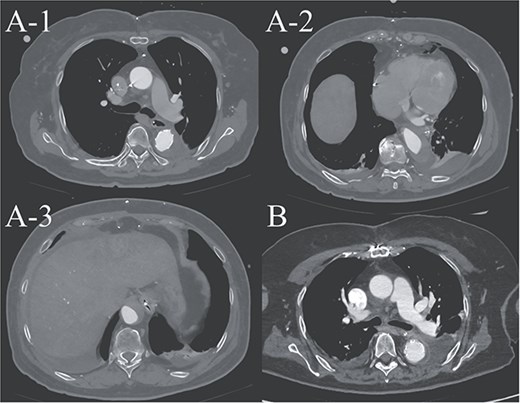

(A-1–3) contrast-enhanced CT image acquired on postoperative Day 2, showing advanced false lumen thrombosis. (B) Contrast-enhanced CT image acquired on postoperative Day 21, demonstrating further remodeling of the false lumen. This image is at approximately the same level as A-1, and the false lumen's thickness is clearly reduced.

A 70-year-old woman presented to the emergency department with sudden-onset chest and back pain. Contrast-enhanced CT revealed an ATAAD extending from the ascending aorta to the bilateral common iliac arteries. The primary entry tear extended from the ascending aorta into the aortic arch, and the false lumen remained patent throughout its entire peripheral extent (Fig. 1). Both renal arteries originated from the true lumen, and there was no malperfusion. Vital signs were stable, and the patient was not in shock. The patient underwent emergency total arch replacement with FET implantation using a 27 × 90 mm FROZENIX four-branched graft (Japan Lifeline Co., Ltd, Tokyo, Japan). The procedure was completed in 7 h and 6 min without intraoperative complications. Postoperatively, urine output declined markedly. Serum creatinine increased from a baseline of 0.81 to 2.61 mg/dl on postoperative Day 1. Diuretics failed to improve urine output, and renal replacement therapy was initiated. Contrast-enhanced CT on postoperative Day 2 showed no signs of renal malperfusion. Although the renal medulla exhibited normal enhancement, a diffuse non-enhancing area throughout the renal cortex—referred to as the “reverse rim sign”—was observed, consistent with RCN (Fig. 2). Thrombosis of the false lumen in the descending thoracic and thoracoabdominal aorta had progressed (Fig. 3). The patient developed persistent coagulopathy, with sustained hypofibrinogenemia and thrombocytopenia. On postoperative Day 2, the platelet count was 4.1 × 104/μl, D-dimer 13.5 μg/ml, and PT-INR 1.54, yielding an International Society on Thrombosis and Hemostasis DIC score of 6, consistent with overt DIC. Anticoagulation therapy with heparin and warfarin was administered. Ultimately, by postoperative Day 50, a total of 36 units of fresh frozen plasma and 100 units of platelets had been transfused; however, coagulation parameters gradually normalized thereafter, and no further transfusions were required (Fig. 4). A follow-up CT on postoperative Day 21 demonstrated further remodeling of the thrombosed false lumen. Brain magnetic resonance imaging performed on postoperative Day 9 to investigate delayed emergence revealed multiple scattered small acute ischemic infarctions involving the cerebellum, brainstem, and cerebral cortex (Fig. 5). These were not attributed to large-vessel occlusion but rather to systemic microthrombotic emboli. Despite supportive care, renal function did not recover, and maintenance dialysis was initiated. The patient was transferred to another hospital on postoperative Day 182.

This case illustrates the development of DIC following total arch replacement with FET implantation for ATAAD, leading to systemic microthrombotic embolism with resultant RCN and diffuse cerebral infarctions. In ATAAD, exposure of circulating blood to the dissected medial layer promotes coagulation cascade activation [1]. Postoperative factors such as cardiopulmonary bypass, heparin administration, and hypothermia further exacerbate the coagulopathic state. In particular, FET implantation is known to facilitate early remodeling of the distal aorta, and the associated extensive thrombosis may accelerate the consumption of coagulation factors, precipitating DIC [2]. Postoperative DIC is associated with increased mortality and serves as an indicator of poor prognosis [3].